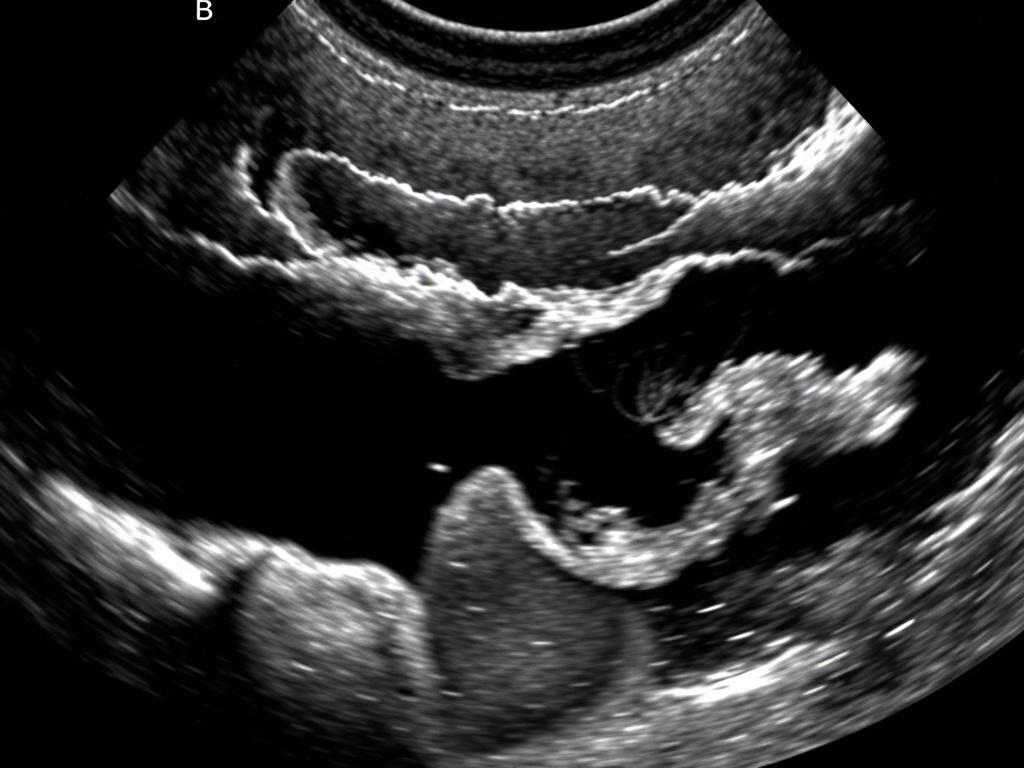

| Холецистит (острый) | Утолщение стенки пузыря, перихолецистическая жидкость, камень в шейке | Боль и лихорадка в сочетании с находкой — повод к экстренной консультации |

Пример 2 — острый холецистит: Желчный пузырь резко увеличен, стенка утолщена до 6 мм, выявлена перихолецистическая жидкость. В просвете — эхогенное образование с акустической тенью, фиксированное в области шейки. Признаки воспаления соответствуют острому холециститу. Поджелудочная без значимых изменений.